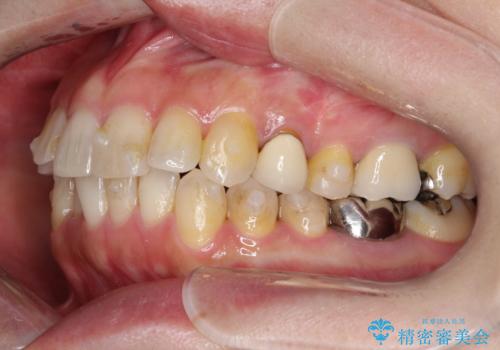

- 前歯のがたつきを主訴に来院されました。

なるべく目立たない矯正をご希望されたので、インビザラインにて治療することとなりました。